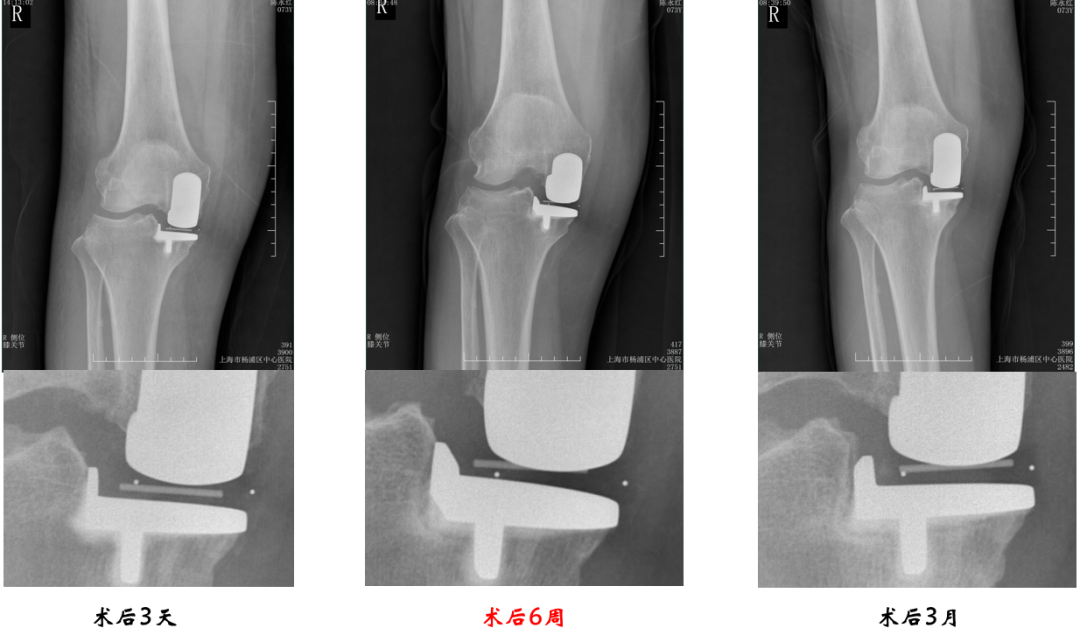

病例1:胫骨假体后倾角度>7°

问题:胫骨假体后倾角度12°,轻度膝外翻

病例1:胫骨假体翻修

UKA to UKA 更换胫骨假体

病例2:胫骨假体松动

病例2:单髁翻单髁

病例3:胫骨假体下沉

病例3:单髁翻单髁